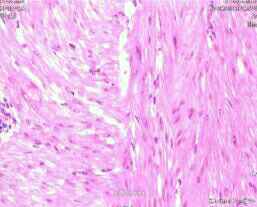

诊断:阴道肿块,性质待查 治疗:术前相关检查未见明显异常,于10月23日硬膜外麻醉下行阴道壁肿物切除术。术中探查见:阴道前壁见一肿物凸起,大小约3 cm *3 cm,质地 中等,活动度尚可。术中冰冻病理检查示:阴道前壁肿物平滑肌瘤。

随访:患者术后恢复好,无任何不适,于10月27日出院。患者术后未进行任何治疗,术后1个月到我院门诊复查阴道彩色超声检查,结果示未见明显异常。 讨论:阴道肿瘤是一种罕见肿瘤,包括乳头状瘤、血管瘤、黏液息肉,罕见平滑肌瘤。阴道平滑肌瘤为良性肿瘤,起源于阴道血管平滑肌、黏膜下平滑肌及圆韧带的平滑肌,或起自于间充质干细胞向平滑肌方向分化,该肿瘤治疗效果确切,一般不容易复发。